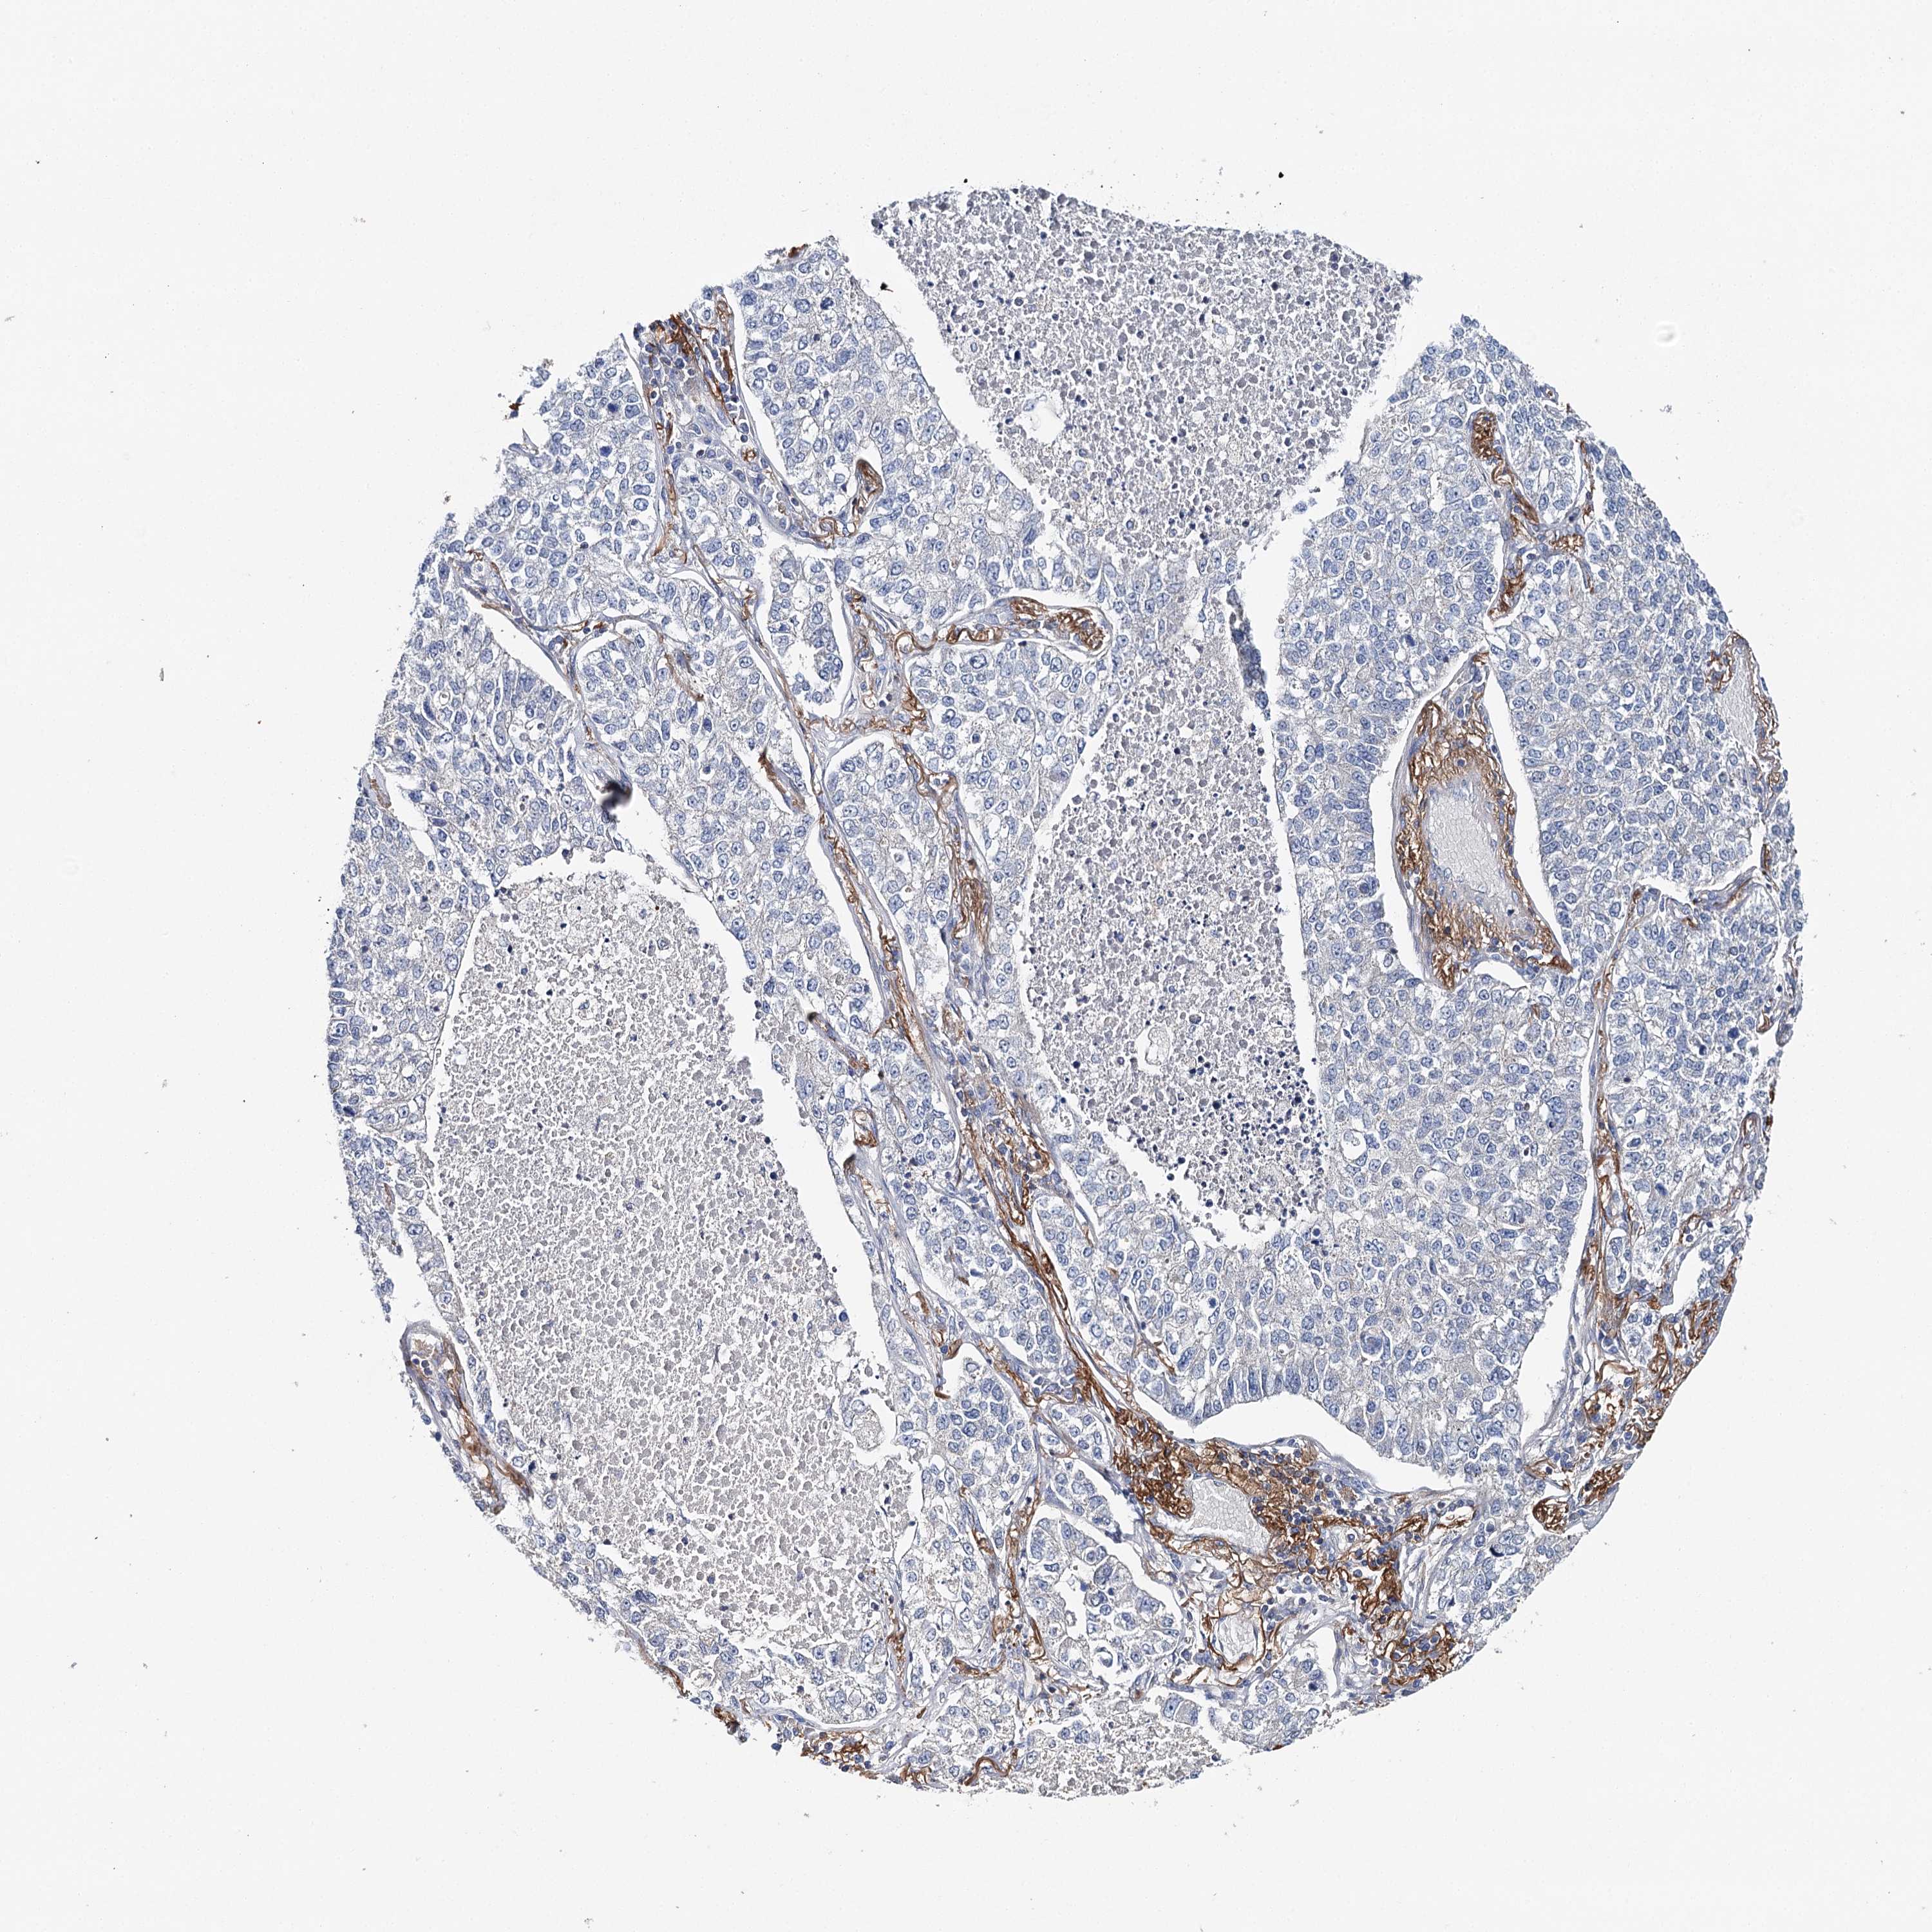

CANCER LUNG CANCER Show tissue menu

LUAD TCGA LUAD VALIDATION LUSC TCGA LUSC VALIDATION PROTEIN LUAD CPTAC PROTEIN LUSC CPTAC PROTEIN EXPRESSION

ANTIBODIES

AND

VALIDATION